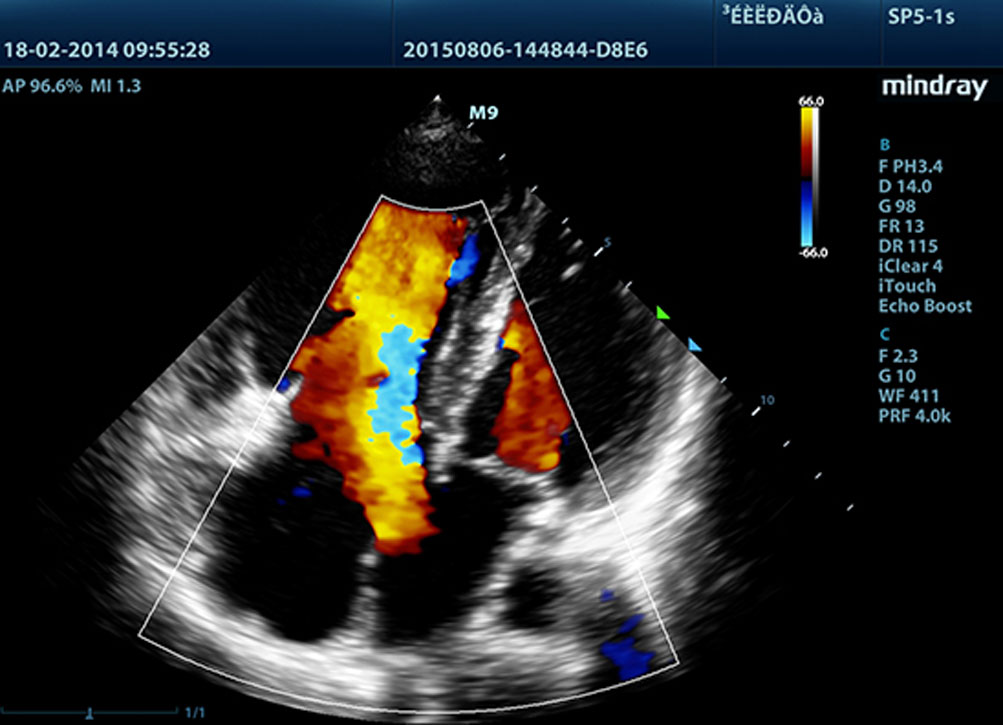

LVO dengan Stress Echocardiography

Kemampuan premium M9 memungkinkan opasifikasi LV pada saat terjadi tekanan. Fitur tersebut memaksimalkan perbedaan antara jaringan miokardial dan blood pool, sehingga permukaan endokardial terlihat lebih jelas. Fitur Stress Echo pada M9 mencakup paket lengkap untuk ekokardiologi beban farmakologis dan beban latihan. Paket ini didukung sistem laporan fleksibel yang dapat dioptimalkan sesuai dengan setiap kebutuhan.